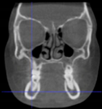

Three points determined the Acta plane: O, F right (FR), and F left (FL) (Table 2). Point O is the midpoint between the most craniodorsal point of the dorsum Sella and the most posterior dorsal point of the Basion in the midsagittal plane (Figure 1). Both points F are a result of the intersection between two lines: the line that connects the most inferior points of the lower orbital margins, right and left, and a line perpendicular to this line that runs through the most external points of the orbital margins, right and left (Figure 2). The new transverse reference plane, the Acta plane (Figure 2), is created by connecting the O-point (Figure 1) with FR and FL (Figure 2).

Figure 2.

(A) Construction of the F-points (right and left), frontal view. The F-points are originated from the intersection between the line connecting points A (the most inferior point of the lower orbit) and the perpendicular line to it that passes through points B (most external/lateral point of the Orbita). (B) Transverse view of the ACTA plane.